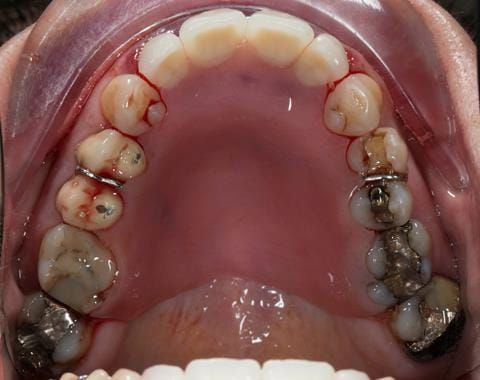

- Other than the maxillary incisors the remaining dentition was in marginally better condition being moderately to heavily restored. Many will probably require replacement and restoration from time to time mainly from wear and tear owing to occlusal forces.

- Extract the upper 2-2 teeth and replace with an interim acrylic based partial denture. Reline the interim denture over 9 - 12 months, replacing with a definitive cobalt chromium based partial denture. The definitive denture would ideally be designed as an occlusal protective splint to reduce the the potential for mechanical wear and breakages of the moderately/heavily restored maxillary dentition. In addition, should further upper teeth require extraction they could be added on to the denture cobalt chromium framework - therefore a new prosthesis would not be required as future teeth are lost. This option would produce an excellent aesthetic outcome. This is the option the patient chose to have.

Following consultation and second discussion appointment the patient chose to have option 3 namely, a maxillary cobalt chromium based partial denture/protective occlusal splint. The clinical situation and treatment process is shown in detail below with photographs. The patient was successfully rehabilitated with this and her quality of life considerably improved. The clinical work was provided by Finlay and the technical work by Rowan.